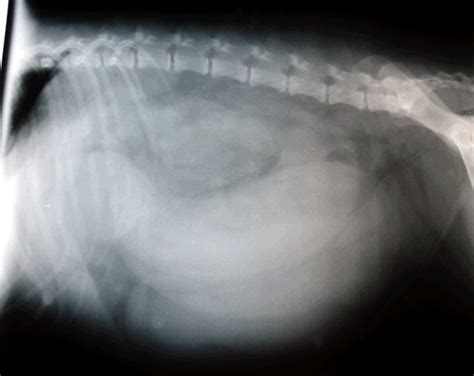

- Ultrazvok trebušne votline: Omogoča pregled reproduktivnih organov, maternice in jajčnikov, kar je ključno pri sumu na piometro ali druge patologije. Kot je svetoval Emir Mujagić, je ultrazvok priporočljiv v primerih, ko sumimo na težave z rodili, še posebej pri starejših psicah ali po carskem rezu.